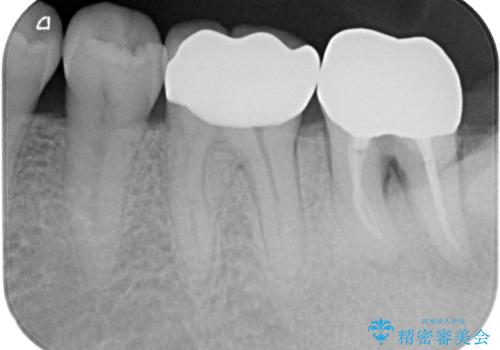

- 奥の銀歯が外れしまったとのことで来院された患者様です。

非常に咬合力が強く、銀歯の周りの歯がむし歯になっている状態でした。

部分的な詰め物ですと、再度周辺がむし歯になるリスクが高いと考えられたため、オールセラミッククラウンにて補綴治療を行うこととしました。

ゴールドのような金属の詰め物は、削る範囲を最小限にし、厚みもセラミックと比べて薄くできるため、セラミックのようにクラウンにせずに治療を行うこともできますが、保険診療である銀歯では、どうしても適合が悪く隙間ができてしまうので、今回のような周辺がむし歯になる可能性が高くなってしまいます。